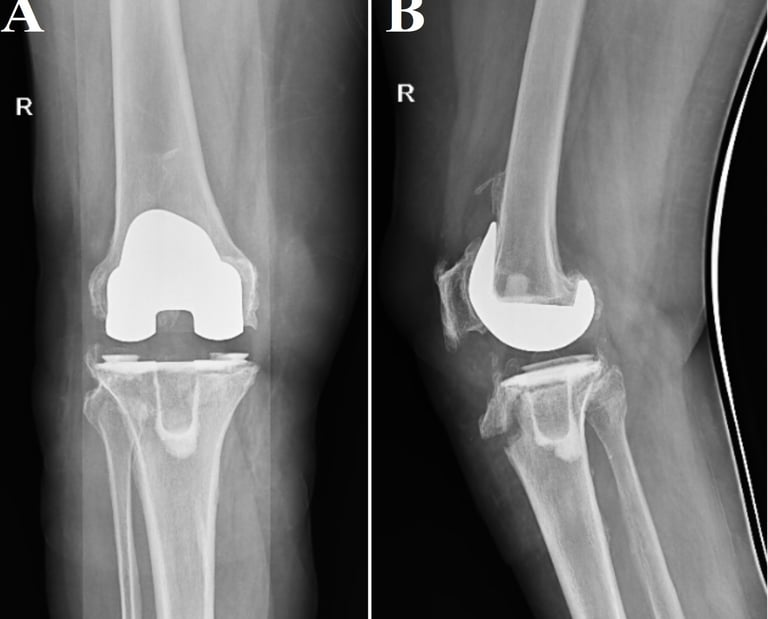

Total knee arthroplasty with long tibial stem for tibial stress fractures with knee osteoarthritis: Two birds with one stone

The treatment and outcome of tibial stress fractures concomitant with knee osteoarthritis (OA) are complicated. The aim of this study was to evaluate the functional and radiological outcome of total knee arthroplasty with long tibial stem as a treatment for patients having knee OA and tibial stress fracture.

Combination-type periprosthetic tibial fracture: Felix type (II+IV)A

Tibial periprosthetic fractures are rare but present a complicated problem for orthopaedic surgeons. Literature in relation to combination-type periprosthetic fractures is extremely scarce, and there is limited guidance available on its treatment. We report the case of a woman in her 60s, whose radiographs revealed a periprosthetic fracture of the tibia, which was a Felix type (II+IV)A fracture. Our demonstrated treatment of a Felix type II+IV periprosthetic fracture could be a viable treatment option for such fractures.